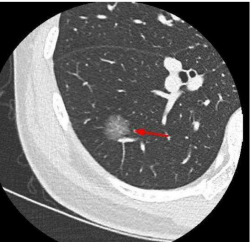

▲根据结节的密度,可以分为

纯磨玻璃结节(类似荔枝果肉)、混合磨玻璃结节(类似荔枝果肉与果核并存)(恶性风险较高)、实性结节(类似荔枝果核)。

纯磨玻璃结节 | 混合磨玻璃结节 | 实性结节 |